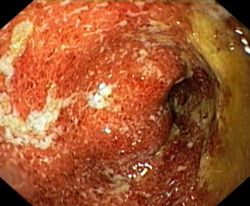

Неспецифический язвенный колит: симптомы, диагностика, диета

Неспецифический язвенный колит – это хроническое небактериальное воспалительное заболевание толстого кишечника с образованием в нем язв. В детском возрасте оно наблюдается относительно редко и протекает крайне тяжело, волнообразно. Мужчины болеют им реже, чем женщины.